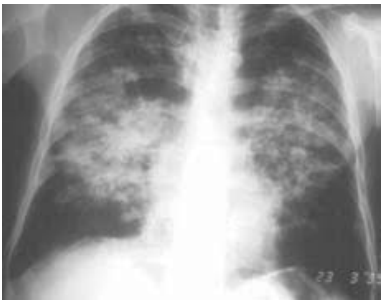

Paciente do sexo masculino, de 56 anos, trabalhou na lavoura a vida toda. Queixa de dispneia progressiva até aos moderados esforços há cerca de um ano, associado com tosse seca, perda de peso, com 5 kg nesse período. Ex-tabagista com uso de 25 maços/ano, parou há 15 anos. Ao exame, encontra-se em bom estado geral, afebril, eupneico, saturação periférica de oxigênio 95%, úlcera em mucosa oral. Feita biópsia da lesão oral, mostrando forma leveduriforme com múltiplos brotamentos, em forma de roda de leme. Traz raio X de tórax realizado.